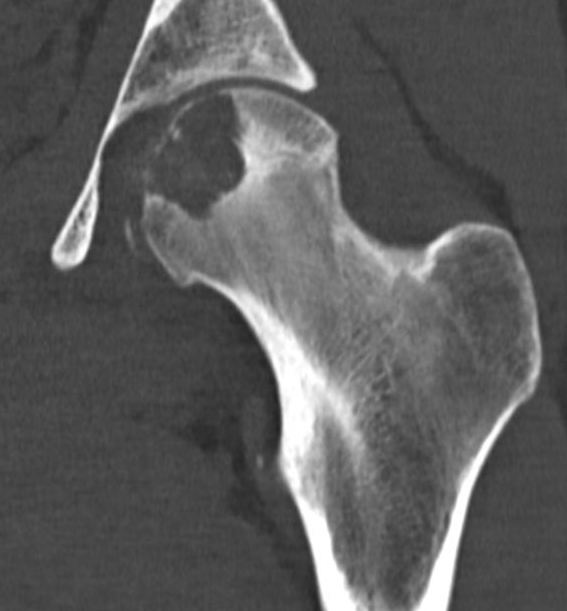

CT

Evaluate articular surface integrity / compromise

Identify chondroid matrix

Well defined eccentrically located epiphyseal lesion

- thin sclerotic reactive rim

- may have calcification